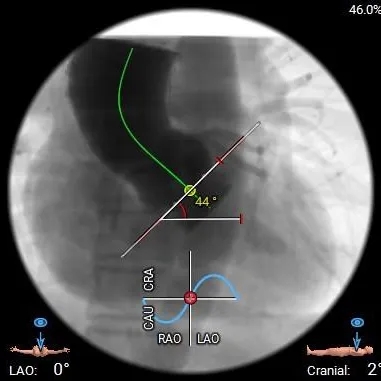

术前CT分析

夹角

瓣环水平夹角:44°

Type0型二叶瓣(左右冠脉异窦),瓣叶增厚,轻度钙化,LVOT偏直筒型;

冠脉开口高度尚可,瓣叶切线测量距离<冠脉开口下缘到根部距离,结合瓦氏窦及STJ预估低冠脉风险;

瓣环水平夹角44°,非横位心,弓角、弓距可,预估输送器可顺利过弓、跨瓣;